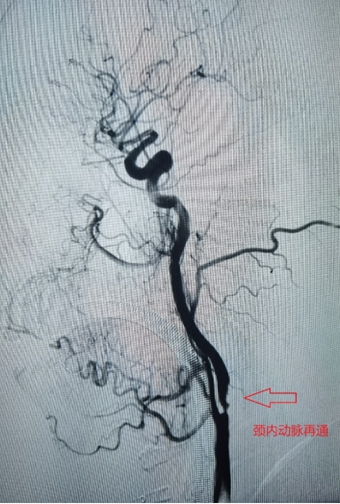

6月7日下午,家住长竹园乡的刘先生突然出现左侧肢体无力,双眼向右侧斜视(凝视),言语不清、口角歪斜等症状,下午3点家属将其送入我院,急诊行头颅CT未见出血,但其右侧颈内动脉末端及大脑中动脉可见高密度征,考虑为大血管病变所致的急性脑梗死,NIHSS评分:14分,mRS评分4分,因无溶栓禁忌,与家属沟通后给予急诊静脉溶栓(阿替普酶,0.9mg/Kg体重)治疗。溶栓大约10分钟左右患者开始出现烦躁,头痛,(NIHSS评分:14分,mRS评分5分)急诊头颅CT未见出血转化,在右侧大脑中动脉供血区出现大片状低密度灶,情况变得更加凶险,卒中团队综合考量认为患者此时急需血管开通治疗以避免脑细胞进一步坏死,再次与患者家属沟通病情后开始急诊取栓治疗。下午3点30分患者被紧急推入介入手术室。

在卒中中心团队的默契配合下,手术顺利取出血栓,实现左侧大脑中动脉完全再通。从动脉穿刺成功到血管完全再通历时仅40分钟。术后患者生命体征平稳,术后1周,患者病情稳定,神志清楚,对话流利,凝视症状缓解,NIHSS评分由14分变为8分。